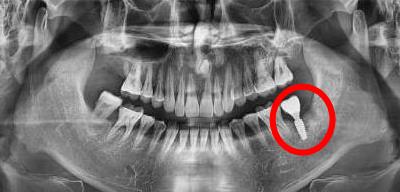

天然牙(左)與(yu) 種植牙結構(右)

當然,一般來說,一顆完整的種植牙是包含下麵的牙根、連接基台部分以及牙冠部分。而上麵介紹的通常是一整顆種植牙的費用,很多醫院都是按照整顆來收費的,建議大家就診前需要谘詢清楚。

種植牙做完後拍片情況